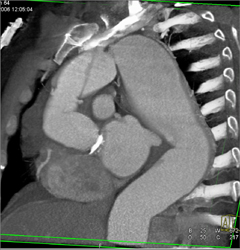

Type A Dissection